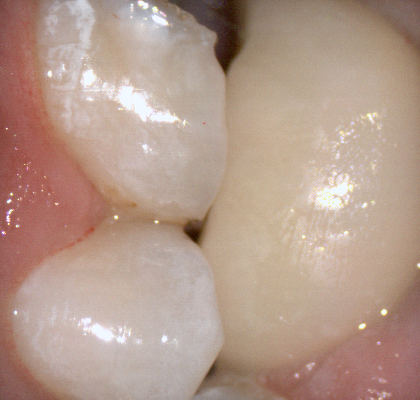

Once you have adequate clearance, retraction, and hemostatis, you can readily image and find your margins in the CAD software